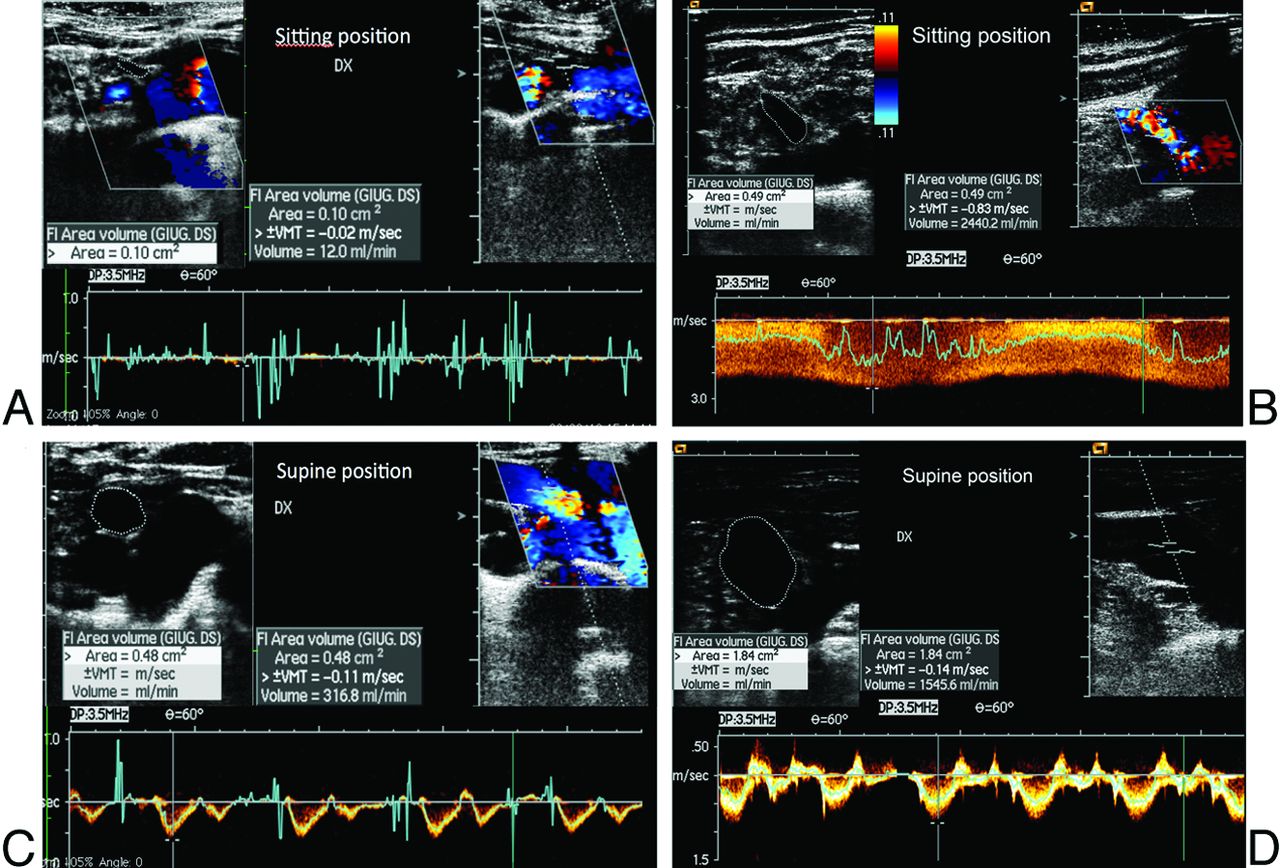

The ΔCVF was evaluated in all the subjects. The outflow of the internal jugular and vertebral veins was calculated from the time average velocity (TAV) and the cross-sectional area (CSA) of the vessel (CVF = CSA × TAV). The time average velocity was measured during a minimum of 3 cardiac cycles at the end of the expiratory phase.21⇓–23 The CVF of each vein was calculated in both clinostatism and the seated position. The sum of all the venous flows was then calculated in clinostatism and the seated position (Fig 1). The difference between the clinostatism and seated position is the ΔCVF value.17

Quantitative evaluation of CVF in the supine and sitting positions in HC (A and B) and patients with MS (C and D). The ΔCVF was >503.24 in HC and <503.24 in patients with MS.